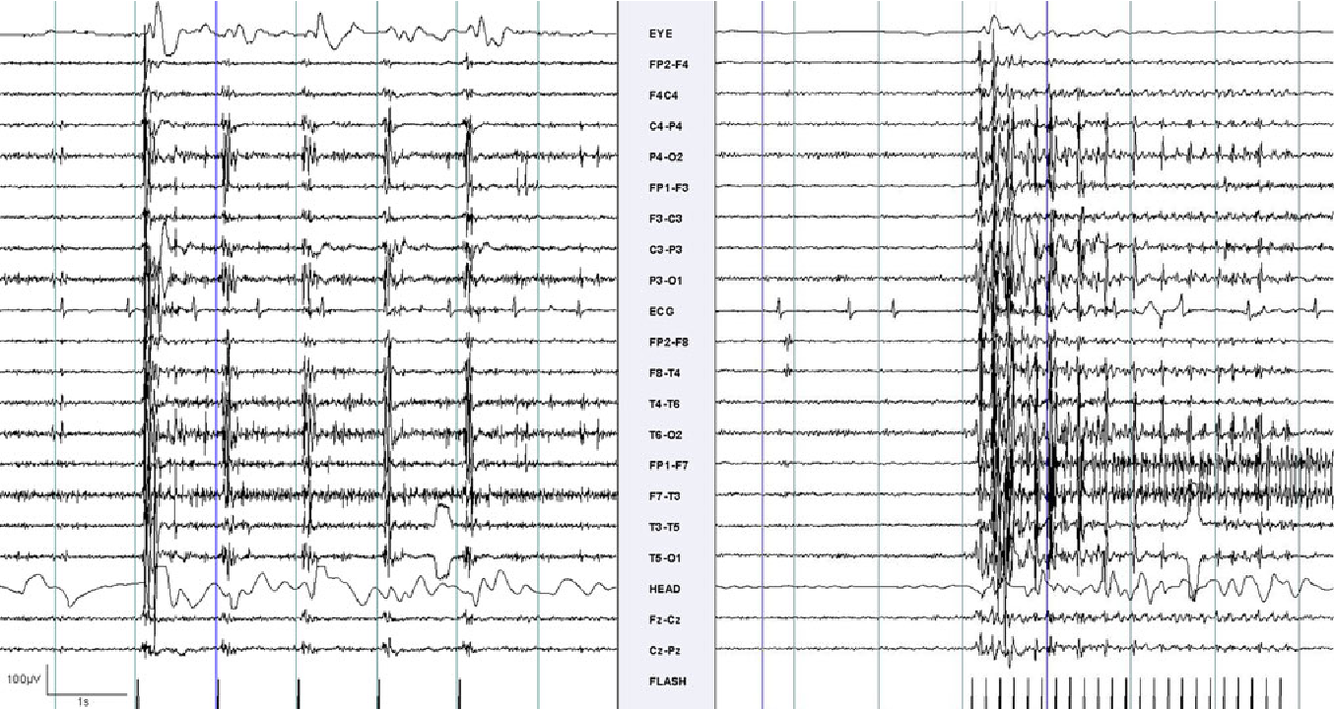

Diagnosis?

SSPE

EEG pattern in Subacute Sclerosing Panencephalitis

Periodic complexes composed of high amplitude, bisynchronous and symmetrical polyspike and sharp and slow wave complexes occuring every 4 to 15 seconds